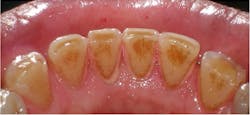

The most common extrinsic stain is yellow stain.1 Clinically, it appears as a dull, yellowish discoloration of plaque (figure 1). Its distribution on tooth surfaces can be generalized or localized. It can be found in people of all ages and is most commonly noted when the patient’s oral hygiene is poor or neglected. The yellow color can be attributed to food pigments.1 Yellow stain can be removed through powered and manual instrumentation as well as polishing procedures. Improved oral self-care can lead to reduction in its accumulation.